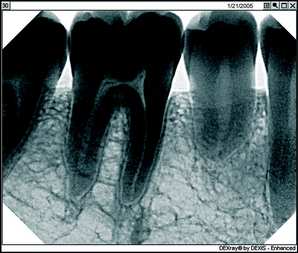

Bottom: Image Enchancement using the Relief Mode

First, there's the critical matter of diagnostic capability. I don't care what other dentists might say who are still trying to convince themselves they should stick with film technology, you can improve your diagnostic capability significantly using digital radiography. With digital, you're looking at an image that fills a 19-inch computer screen and not a film image the size of a postage stamp. Using the software-based digital radiography's image enhancement functions such as magnification, brightness control, and heightened contrast, you can bring out aspects of the X-ray that simply aren't visible on film, including such things as tiny fractures and imperfections that you might very well miss on film. Once you begin to practice using magnification for vision, you wouldn’t practice without it. It’s the same with the digital x-rays.